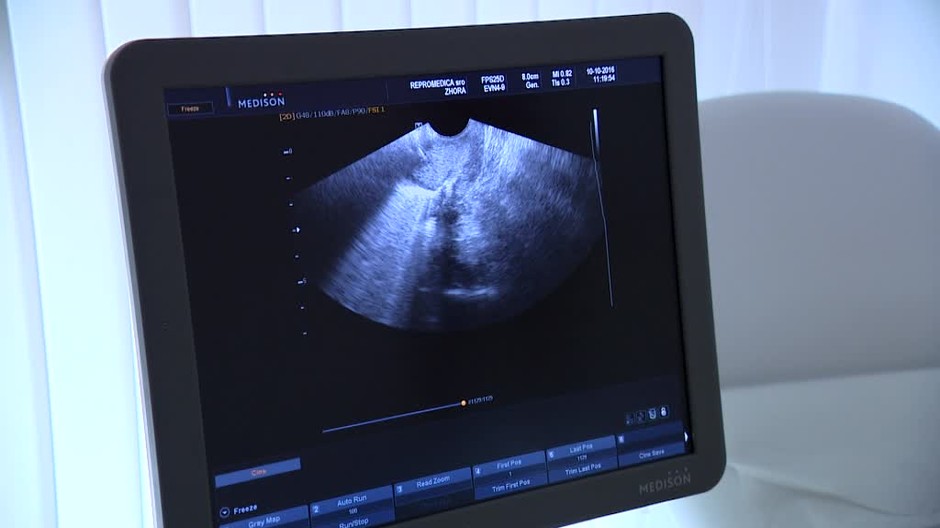

Prípadom smrti 33-ročnej Doroty sa teraz zaoberá krajská prokuratúra v Katoviciach. Žena bola v nedeľu 21. mája prijatá do nemocnice v Nowom Targu po tom, ako jej v piatom mesiaci tehotenstva odtiekla plodová voda. Počas hospitalizácie sa v telefonátoch príbuzným sťažovala, že sa cíti veľmi zle, zvracala a mala zimnicu. V stredu skoro ráno žene diagnostikovali septický šok a sonografickým vyšetrením sa zistilo, že došlo k odumretiu plodu. Žena zomrela v ten istý deň po zástave srdca.